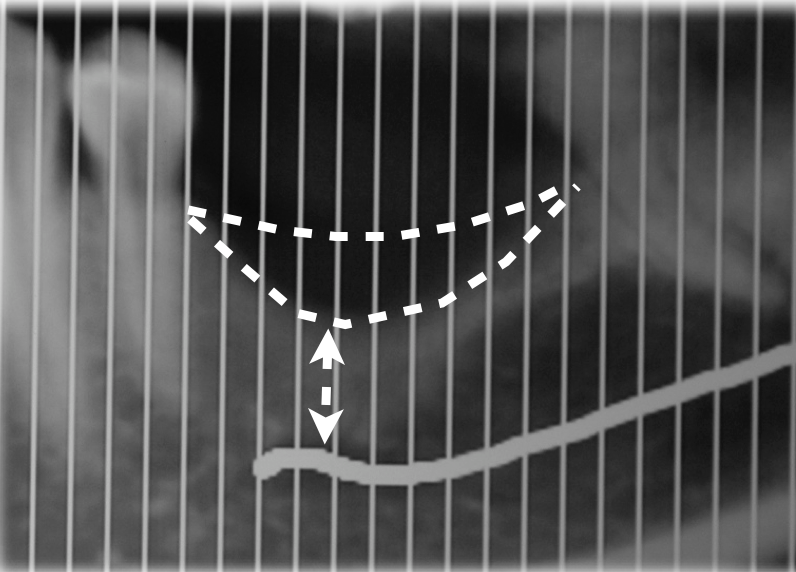

La sezione panoramica mise in evidenza la prossimità della cresta residua con il canale mandibolare (Figg. 3-4), e nei tagli sagittali si poté misurare come in prossimità delle due zone ove sarebbe stato interessante inserire gli impianti (primo premolare e primo molare) i volumi ossei residui non ne consentivano il posizionamento. Nel sito ove si voleva posizionare il primo premolare la distanza tra la cresta ossea e il tetto del canale mandibolare era di 5 mm, inoltre lo spessore della corticale sia vestibolare che linguale era ben rappresentato occupando 4 dei 5 mm disponibili per un eventuale sito implantare, inoltre il forame mentoniero si apriva proprio in corrispondenza di questo sito creando un ulteriore limitazione anatomica. Il sito più posteriore mostrava un ulteriore restringimento in senso sagittale e questo rendeva la clearance verticale 4 mm mentre anche in questo caso le corticali vestibolare e linguale occupavano la grande maggioranza dello spazio disponibile limitando il volume osseo disponibile a una quantità insufficiente a ricevere un impianto. La progettazione chirurgica e protesica del caso prevedeva un intervento con tentativo di ampliare la cresta ossea residua sia in senso orizzontale (almeno a 6/7 mm) che verticale (3/4 mm) per poter accomodare in completa sicurezza impianti della lunghezza di 8.5 mm. In questo caso si decise di optare per un materiale che offrisse la possibilità di ricostruire il volume nelle due dimensioni dello spazio e richiedesse una sola fase chirurgica, la lamina corticale7-11 (Figg. 7-11).

A sei mesi dall’intervento chirurgico la paziente venne sottoposta ad una nuova CBCT di controllo e questa evidenziò come i volumi stavano cambiando e l’osso innestato si stava mineralizzando al di sotto della lamina corticale, in bianco si nota la variazione volumetrica rispetto a quella che era la condizione iniziale (in blu) (Fig. 13). A dodici mesi dal primo intervento si decise di intervenire per inserire nella zona due impianti come da progetto iniziale, dopo aver anestetizzato la paziente con Articaina 1:200.000 una nuova incisione a mezza cresta permettè di scostare i lembi vestibolari e linguali per esporre la nuova cresta ossea ora con uno spessore di 8 mm nella parte posteriore e 6 mm nella porzione più anteriore. Questo consentì il posizionamento di due impianti a vite Bredent uno di diametro 4.5 x 8,5 mm di lunghezza (nel sito del molare) e uno di diametro 4 x 8,5 mm di lunghezza nel sito del secondo premolare13 (Figg. 14, 15).